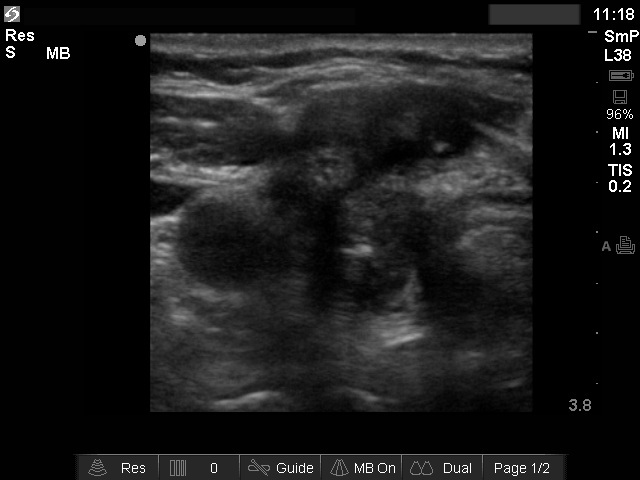

Ultrasonography: there were multiple hypoechogenic lesions containing amorphous hyperechogenic granules in both resected lobes. The lesions were avascular.

Aspiration cytology resulted in benign granulation around surgical thread.